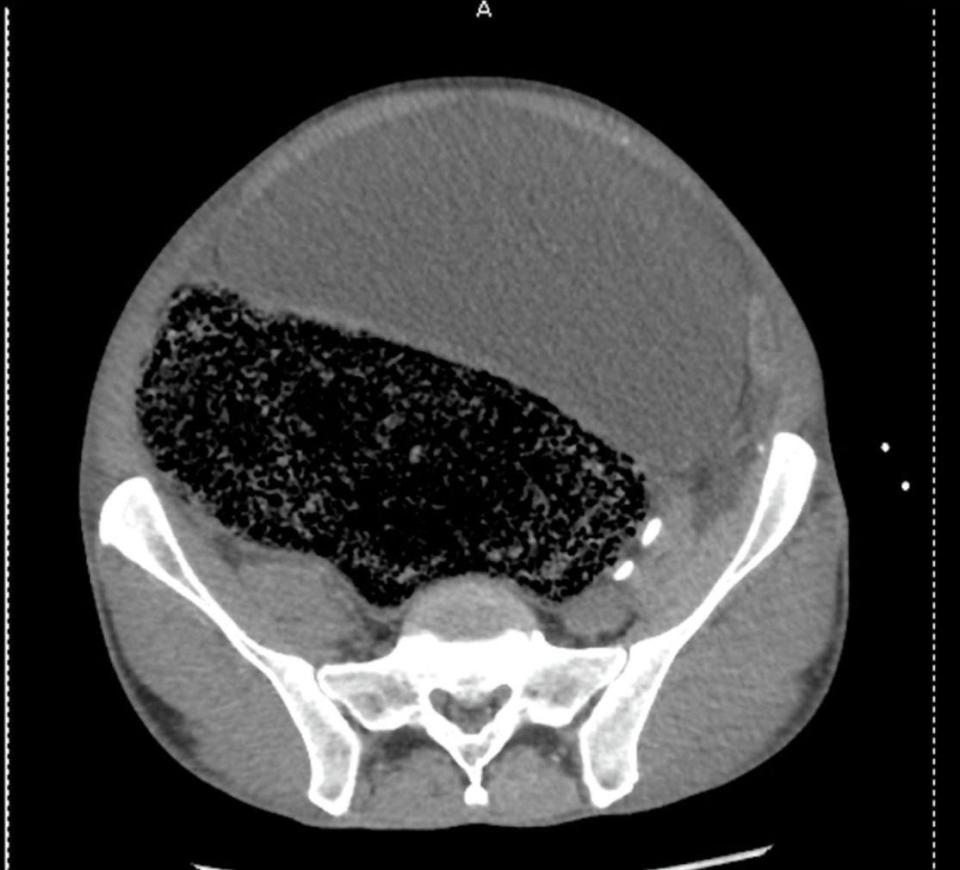

5. Tahan buang air besar selama 4 minggu, cowok ini nyaris lumpuh

Tahan buang air besar selama 4 minggu, cowok ini nyaris lumpuh